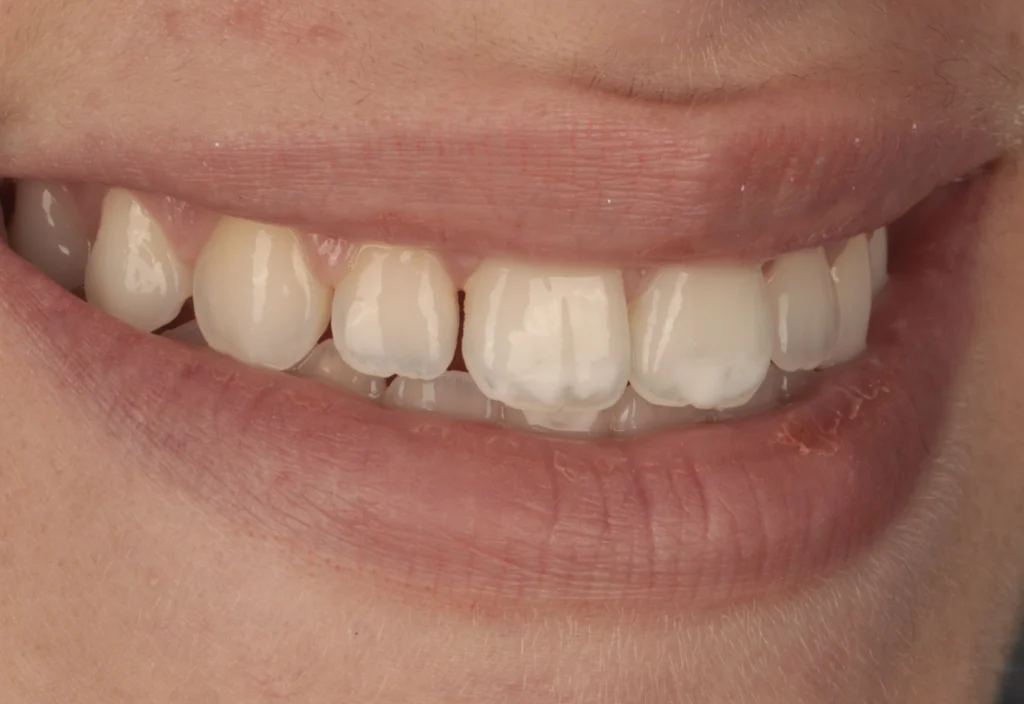

Composite Bonding in Beirut

A simple, fast, and natural solution to improve your smile in one visit.

Composite bonding is a minimally invasive cosmetic treatment used to repair chipped teeth, close gaps, and improve shape and color. Using high-quality materials and precise techniques, we can restore your teeth in a single session with results that blend seamlessly with your natural smile.